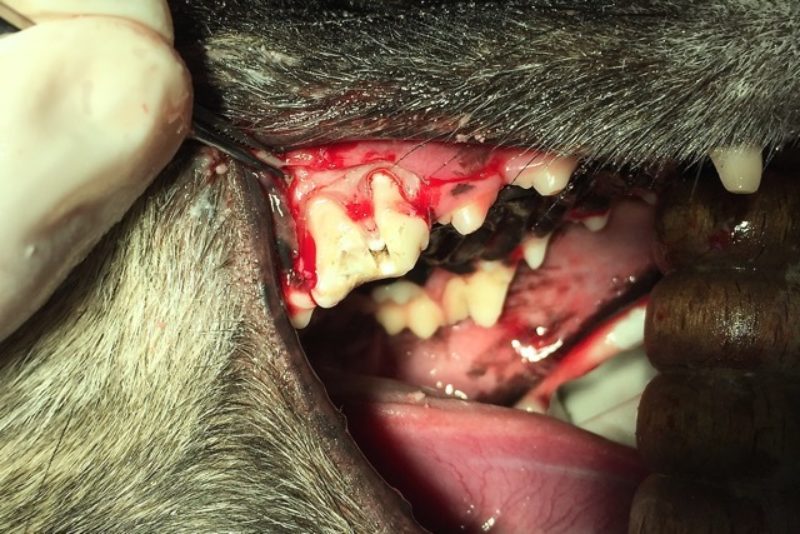

Bei „Lotte“ lag jedoch eine komplizierte Fraktur mit gespaltener Krone vor, so dass tatsächlich nur eine Extraktion des Zahnes in Frage kam. Solch ein dreiwurzeliger Zahn kann nicht im Ganzen gezogen werden. Die Wurzeln sitzen fest im Kiefer und sind gerade bei schon älteren infizierten Zähnen sehr spröde und morsch und brechen leicht in der Tiefe ab. Daher ist eine kieferchirurgische, offene Extraktion die Methode der Wahl. So wurde bei „Lotte“ die Mundschleimhaut um den Zahn herum gelöst und der Kieferknochen freigelegt. Dann wurde der Knochen mit einem wassergekühlten Bohrer über den Zahnwurzeln entfernt, bis diese komplett sichtbar waren. Anschließend wurde der Zahn mit einem Fräser in drei Teile geteilt und die einzelnen Wurzeln mit verschiedenen Hebeln gelockert, um sie danach separat ziehen zu können (Foto 2). Besonders wichtig ist es, dass keine Wurzelreste im Kiefer verbleiben, denn diese verursachen weiterhin Schmerzen und führen zu einer Abszessbildung im Kieferknochen. Nach Glättung der scharfen Knochenkanten wurde die Schleimhaut wieder über die Wunde gelegt und mit einer Wundnaht mit Einzelheften eines resorbierbaren Nahtmaterials verschlossen, welches sich nach einigen Wochen von selbst auflöst (Foto 3).